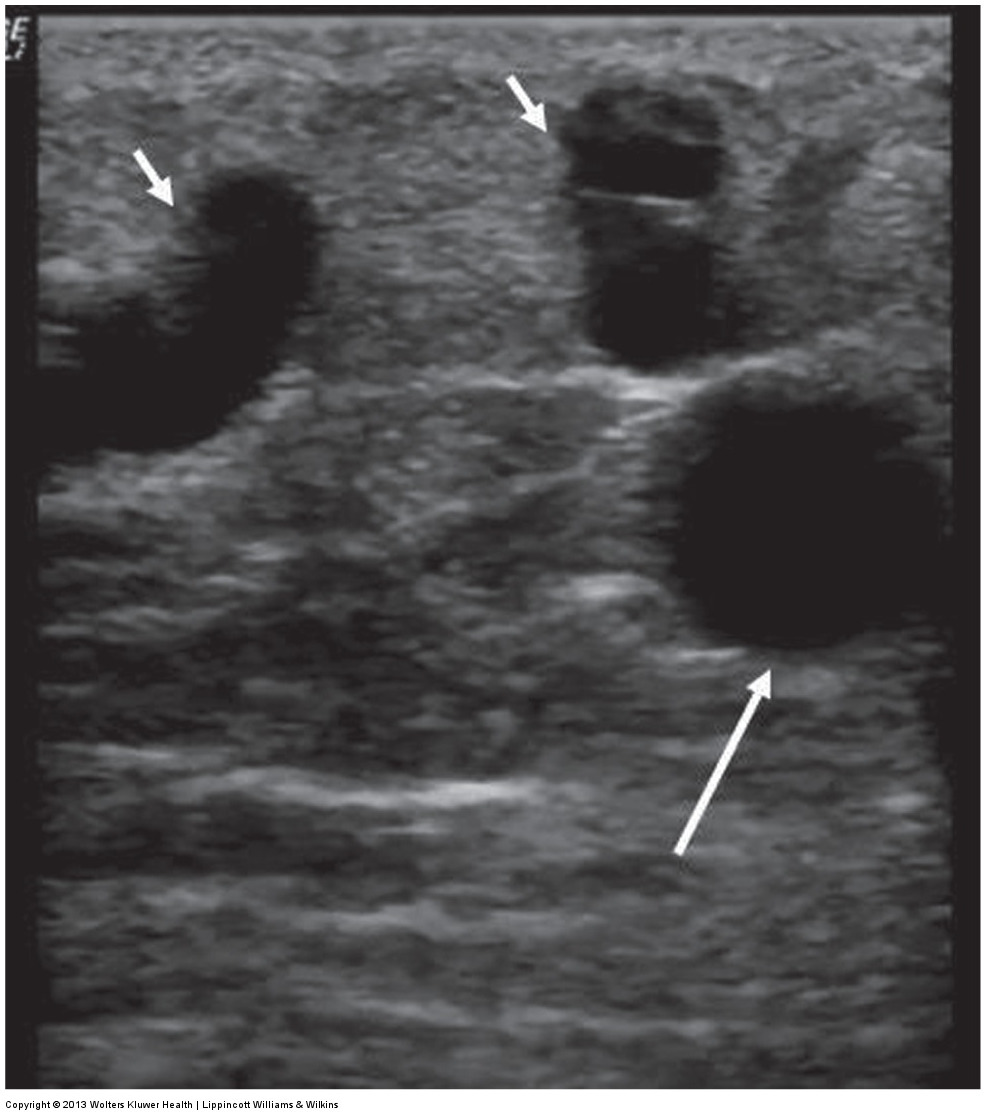

ultrasound of superficial varices with the main system beneath it